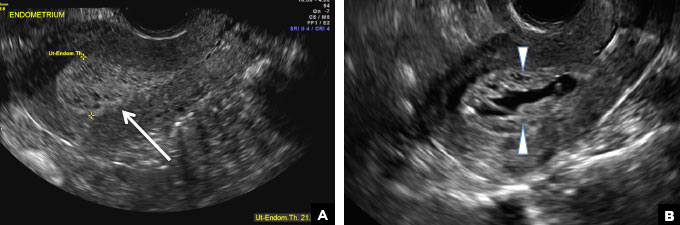

A) Endometrial polyp INCORRECT

Endometrial polyps on ultrasonography appear as focal echogenic (hyperechoic) masses or as nonspecific endometrial thickening.1 Color Doppler often demonstrates a vascular stalk, which is a nonspecific finding that also can be seen in submucosal fibroids and endometrial cancer.2 On sonohysterography (SHG), endometrial polyps typically appear as well-defined echogenic/hyperechoic polypoid lesions (tissue appearance similar to that of normal endometrium) protruding into the endometrial canal but still preserving the endometrial−myometrial interface.2,3

Endometrial polyp. (A) Transvaginal pelvic ultrasound of the uterus with color Doppler demonstrates a focal echogenic lesion with a vascular stalk (long arrows). (B) SHG shows a well-defined polypoid lesion, isoechoic to the endometrium, and protruding into the endometrial canal but still preserving the endometrial−myometrial interface (short arrow). (C) 3D SHG imaging shows the echogenic endometrial polyp (short arrow) and an incidental intramural fibroid in the fundus (arrowhead).